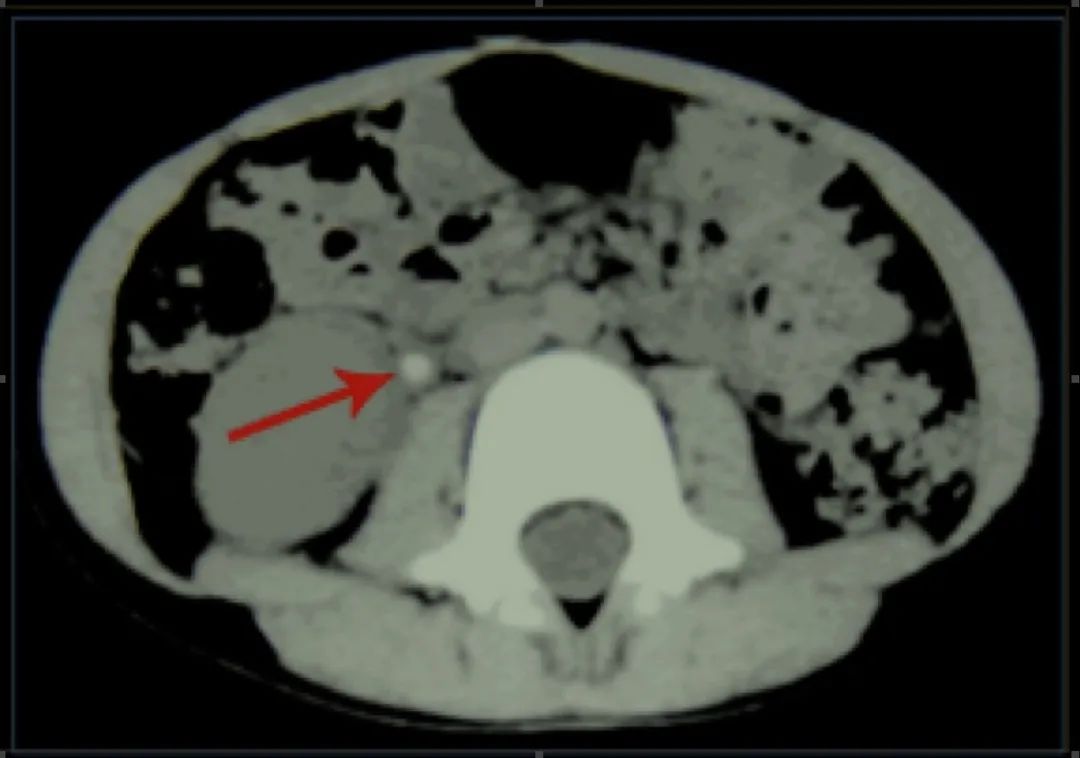

螺旋CT可进行无漏层连续扫描,非常精确,是诊断上尿路结石最可靠的影像学方法。肾绞痛发作后,螺旋CT常可显示肾包膜下积液,这是诊断急性肾绞痛的有力佐证。

泌尿系CT可清晰显示右侧输尿管上段结石